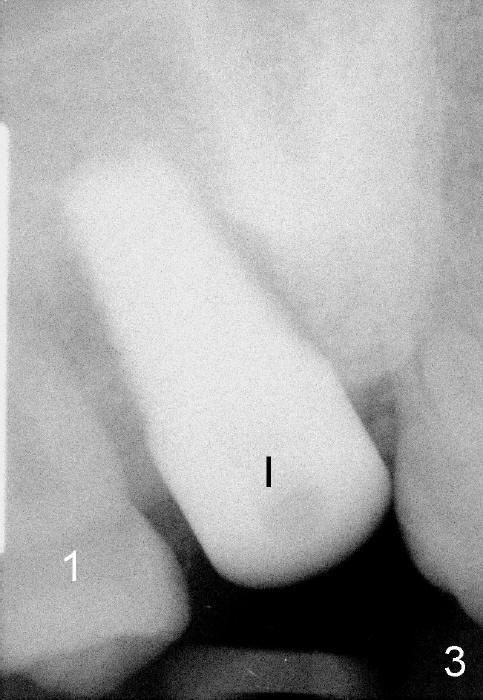

A 48-year-old lady is a dental phobic and has generalized chronic periodontitis. Bone loss around the tooth #2 has been severe for the last 5 years (Fig.1,2 *). Finally she agrees to have #2 (symptomatic) extracted and immediate implant placed (Fig.3 I). A 7x17 mm implant has to be used to achieve primary stability. The remaining buccal and lingual gaps are filled with allograft and membrane (Fig.4 *). Fig.5 shows that there is a space between the tooth #1 (asymptomatic) and the immediate implant (I). The wound/socket is protected by applying perio dressing around an abutment (Fig.6 A). Postop the patient is pain free; the perio dressing dislodges by itself. She returns 3.5 months later for restoration; but the tooth #1 has shifted mesially (Fig.6 arrow). The patient is not so willing to have #1 removed. Bands and bracket are placed in the neighboring teeth including a provisional crown to move the shifted tooth (with mobility) distally (Fig.7,9). The 2nd reason for #1 shifting is abnormal occlsual scheme on the right posterior region (Fig.8); mobility of #1 is the 1st one. The 3rd one is probably bruxism. In 5-6 weeks, the tooth #1 has moved to a desirable position (Fig.10, as compared to Fig.3,5). There is enough space for restoration (Fig.11,12).